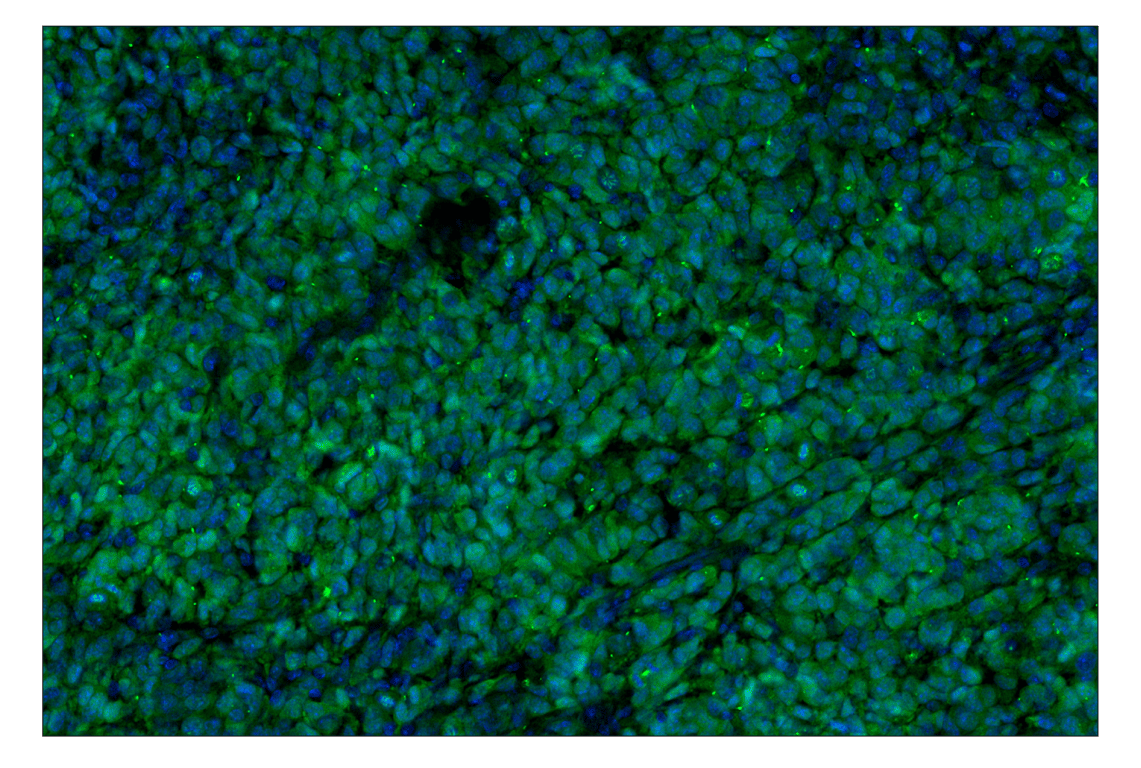

p16 INK4A (F2T7H) Rabbit Monoclonal Antibody (Alexa Fluor® 488 Conjugate) #38083

Immunohistochemistry (Paraffin) 1:50 - 1:200

p16 INK4A (F2T7H) Rabbit Monoclonal Antibody (Alexa Fluor® 488 Conjugate) recognizes endogenous levels of total p16 INK4A protein. This antibody does not cross-react with p15 INK4B protein. Non-specific cytoplasmic staining was observed in mouse small intestine epithelium by immunohistochemistry.